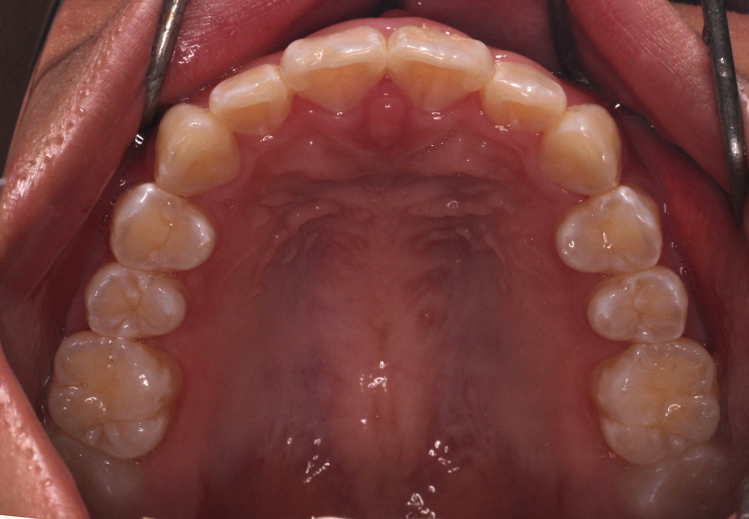

最後のアライナーが終わった時の口腔内写真です。

前歯のがたつきはなくなり、カリエール後にできていた隙間もなくなっています。

奥歯も1歯対2歯の関係で咬めていることがわかります。

通常は歯の並びを微調整するために口腔内を再スキャンし、歯の並びを再設計すること(リファイメント) を2,3回行いますが今回のケースは一回目で満足のいく結果が得られたのでここで保定期間に入りました。